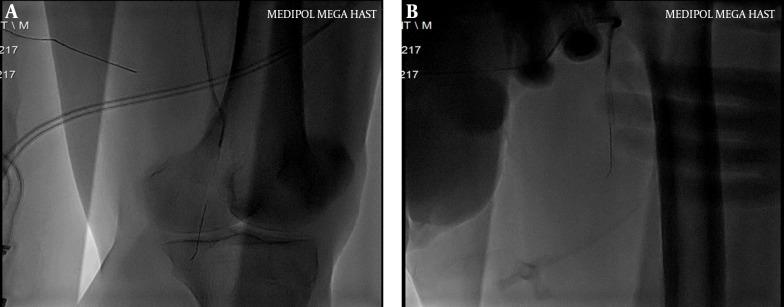

We present a case of a distally embolized catheter fragment that was percutaneously retrieved. The catheter fragment was tightly held by the inflated balloon, moved together with the system, and successfully retrieved out of the circulation via the femoral sheath. Considerable distal embolization of the foreign body and retrieval with the balloon dilatation technique are the unique features of this case.

我们报告一例经皮取出远端栓塞导管碎片的病例。导管碎片被充气的球囊紧紧夹住,与系统一起移动,并通过股鞘成功从循环中取出。异物的大量远端栓塞以及通过球囊扩张技术取出是本病例的独特特征。